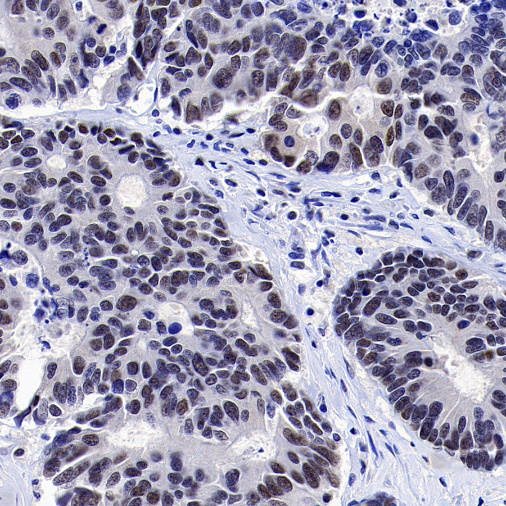

Positive staining

IHC shows positive staining in paraffin-embedded human colon

IHC shows positive staining in paraffin-embedded human testis